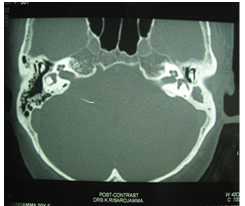

In the presence of clinical mastoiditis, a CT scan should be performed to evaluate for an unappreciated subperiosteal abscess or coalescent mastoiditis (Figure 1 & Figure 2). MRI is also useful in mastoiditis cases (Figure-3), but it is not done routinely. CT scan can demonstrate subperiosteal abscess and possibly the cortical defect in the mastoid.

Figure 1 CT scan picture showing mastoiditis changes on the left side.